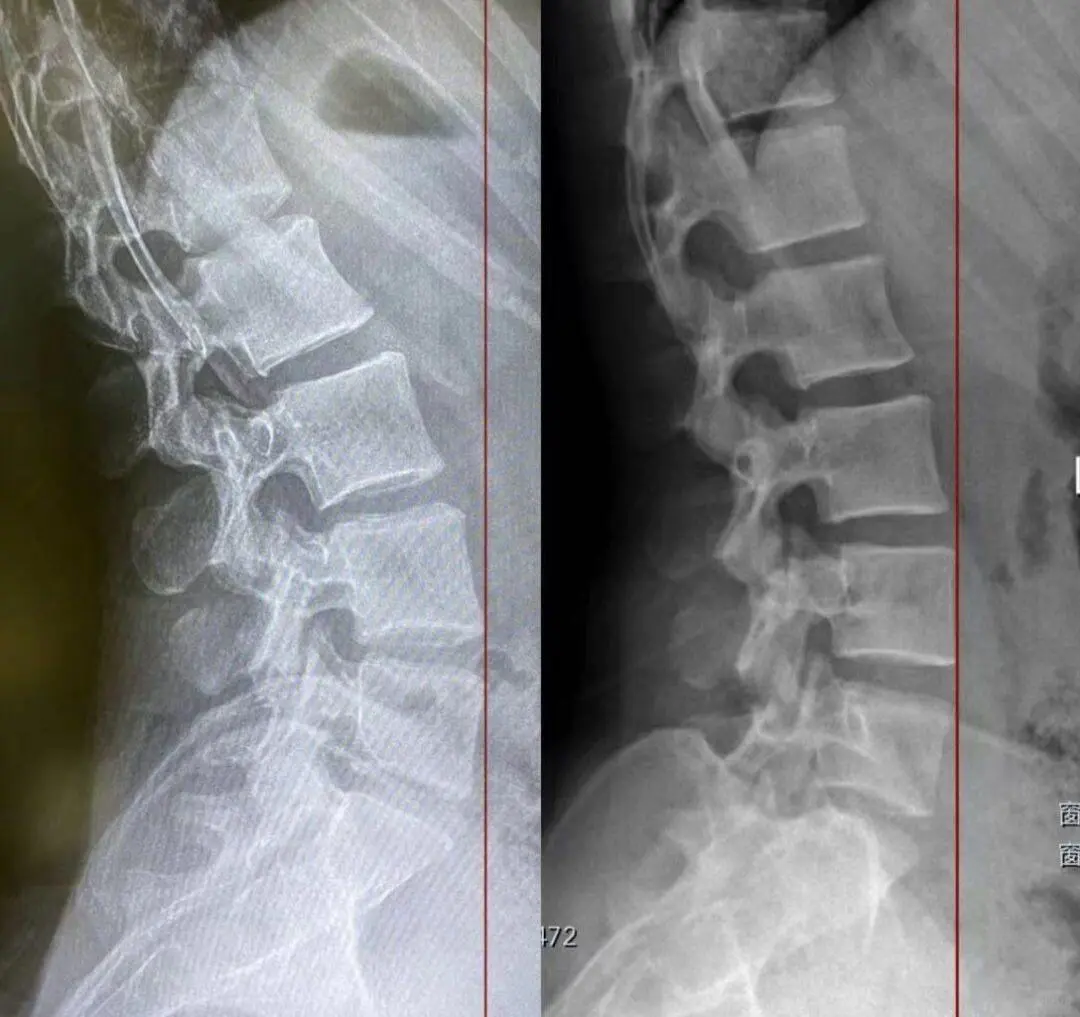

如果𧿹指伸展角度不够,人体会将缺失的工作转移到髋关节或者腰椎上,这种情况常常出现在骨盆前移和腰椎曲度过大的人身上。如图四,网图。

𧿹指的功能测试很简单。坐姿位正常的拇指被动伸展可以达到60-80°;站姿位负重位,伸展角度要小一些,但至少应该达到50°(也有的学派认为站姿是40°)才算合格,如图五。低于50°(或40°)都会导致步态异常,可能会引发髋关节或者腰椎功能障碍。